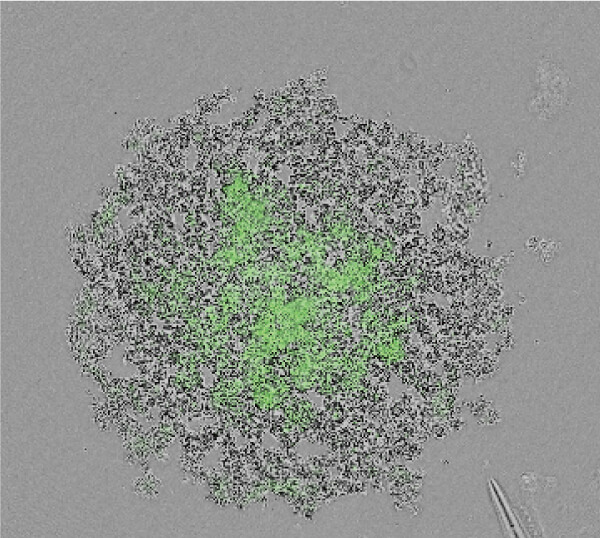

3D解析を用いた形態的定量解析

- 青…DAPI(核を染色)

緑…Ki67(増殖細胞のマーカ) - 形態情報(細胞数、容積、Ki67陽性細胞数)を算出

- 細胞塊あたりの細胞数、細胞密度、増殖細胞の比率が算出することができる。

- F-PDO®の種類により、細胞塊の大きさ、細胞密度、増殖細胞の比率はさまざまである。

| 肺がん | ||

|---|---|---|

| RLUN5 | RLUN16 | RLUN21 |

![]() |